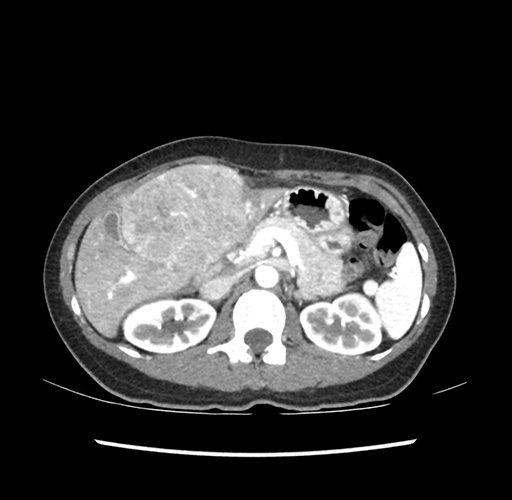

Imaging Analysis

Look through the patient's CT scan to identify any areas of concern for the necessary procedure.

Based on your CT findings, which issue(s) would give reason for "planned slowing down moment(s)" in this case?